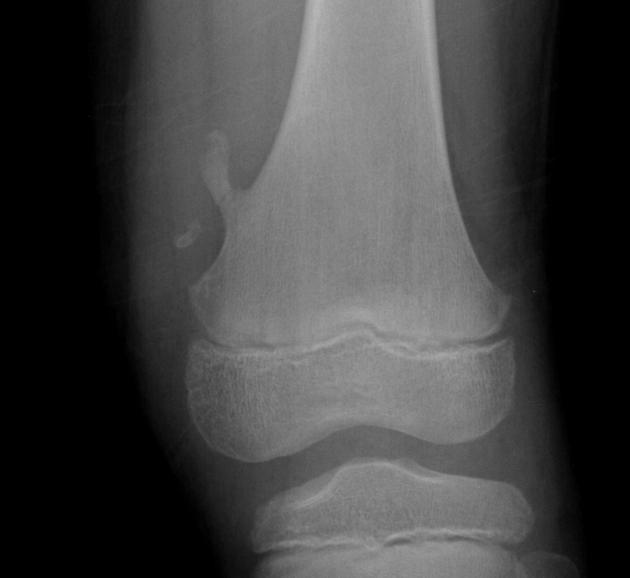

Comminuted Fracture

The bone is broken into 3 or more fragments - common in long bones such as the femur

Bone Cyst

Wall of fibrous tissue filled with fluid - they are asymptomatic - appears as a lucent, oval shape with the long axis parallel to the host bone

A hereditary condition in which failure of the resorptive mechanism of calcified cartilage interferes with its normal replacement by mature bone. Results in a symmetric, generalized increase in bone density

Osteopetrosis (Marble Bone)

The most common benign bone tumor - arises from the growth zone between the epiphysis and diaphysis of long bones (Metaphysis). Most commonly involves the lower femur or upper tibia and is capped by growing cartilage. Many time it is asymptomatic unless the affected long bone is traumatized which results in a pathologic fx. of the diseased bone.

Osteochondroma (Exostosis)